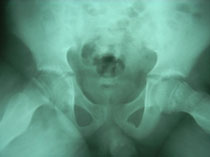

The hip joint consists of two structures: a cup-shaped socket (acetabulum) in the pelvis and a ball-shaped upper end of the thigh bone (femoral head). Normally, these structures fit snugly together and are held in place by ligaments and muscles. In congenital dislocation of the hip (CDH), the femur comes out of the acetabulum. (See Glossary at end for definitions of technical terms.)

There are two categories of CDH, typical, which occurs at birth, and teratologic, which occurs prenatally. If the dislocation is left untreated, permanent problems such as a limp, a short leg, and a diminished range of movement may result.

Diagnosis of CDH: Age 6 weeks to one year As the infant grows the motion of the affected hip will become restricted. That is, abduction will be limited. An x-ray is required to make a diagnosis at this stage.

Diagnosis of CDH: Age 1 year If the child is not treated before the age of 1 year, he or she will walk with a limp and leg abduction (doing the splits) will be restricted. The affected limb will also be shorter than the other. Although the child may appear disabled, pain is uncommon and limitations on leg function are slight. Once again, an x-ray is required to make the diagnosis.

Diagnosis of CDH: Adult The untreated adult will walk with a limp, have legs of unequal length, will a limp, have legs unequal length, will experience fatigue when walking, and may feel pain. Again, an x-ray is useful for diagnosis.